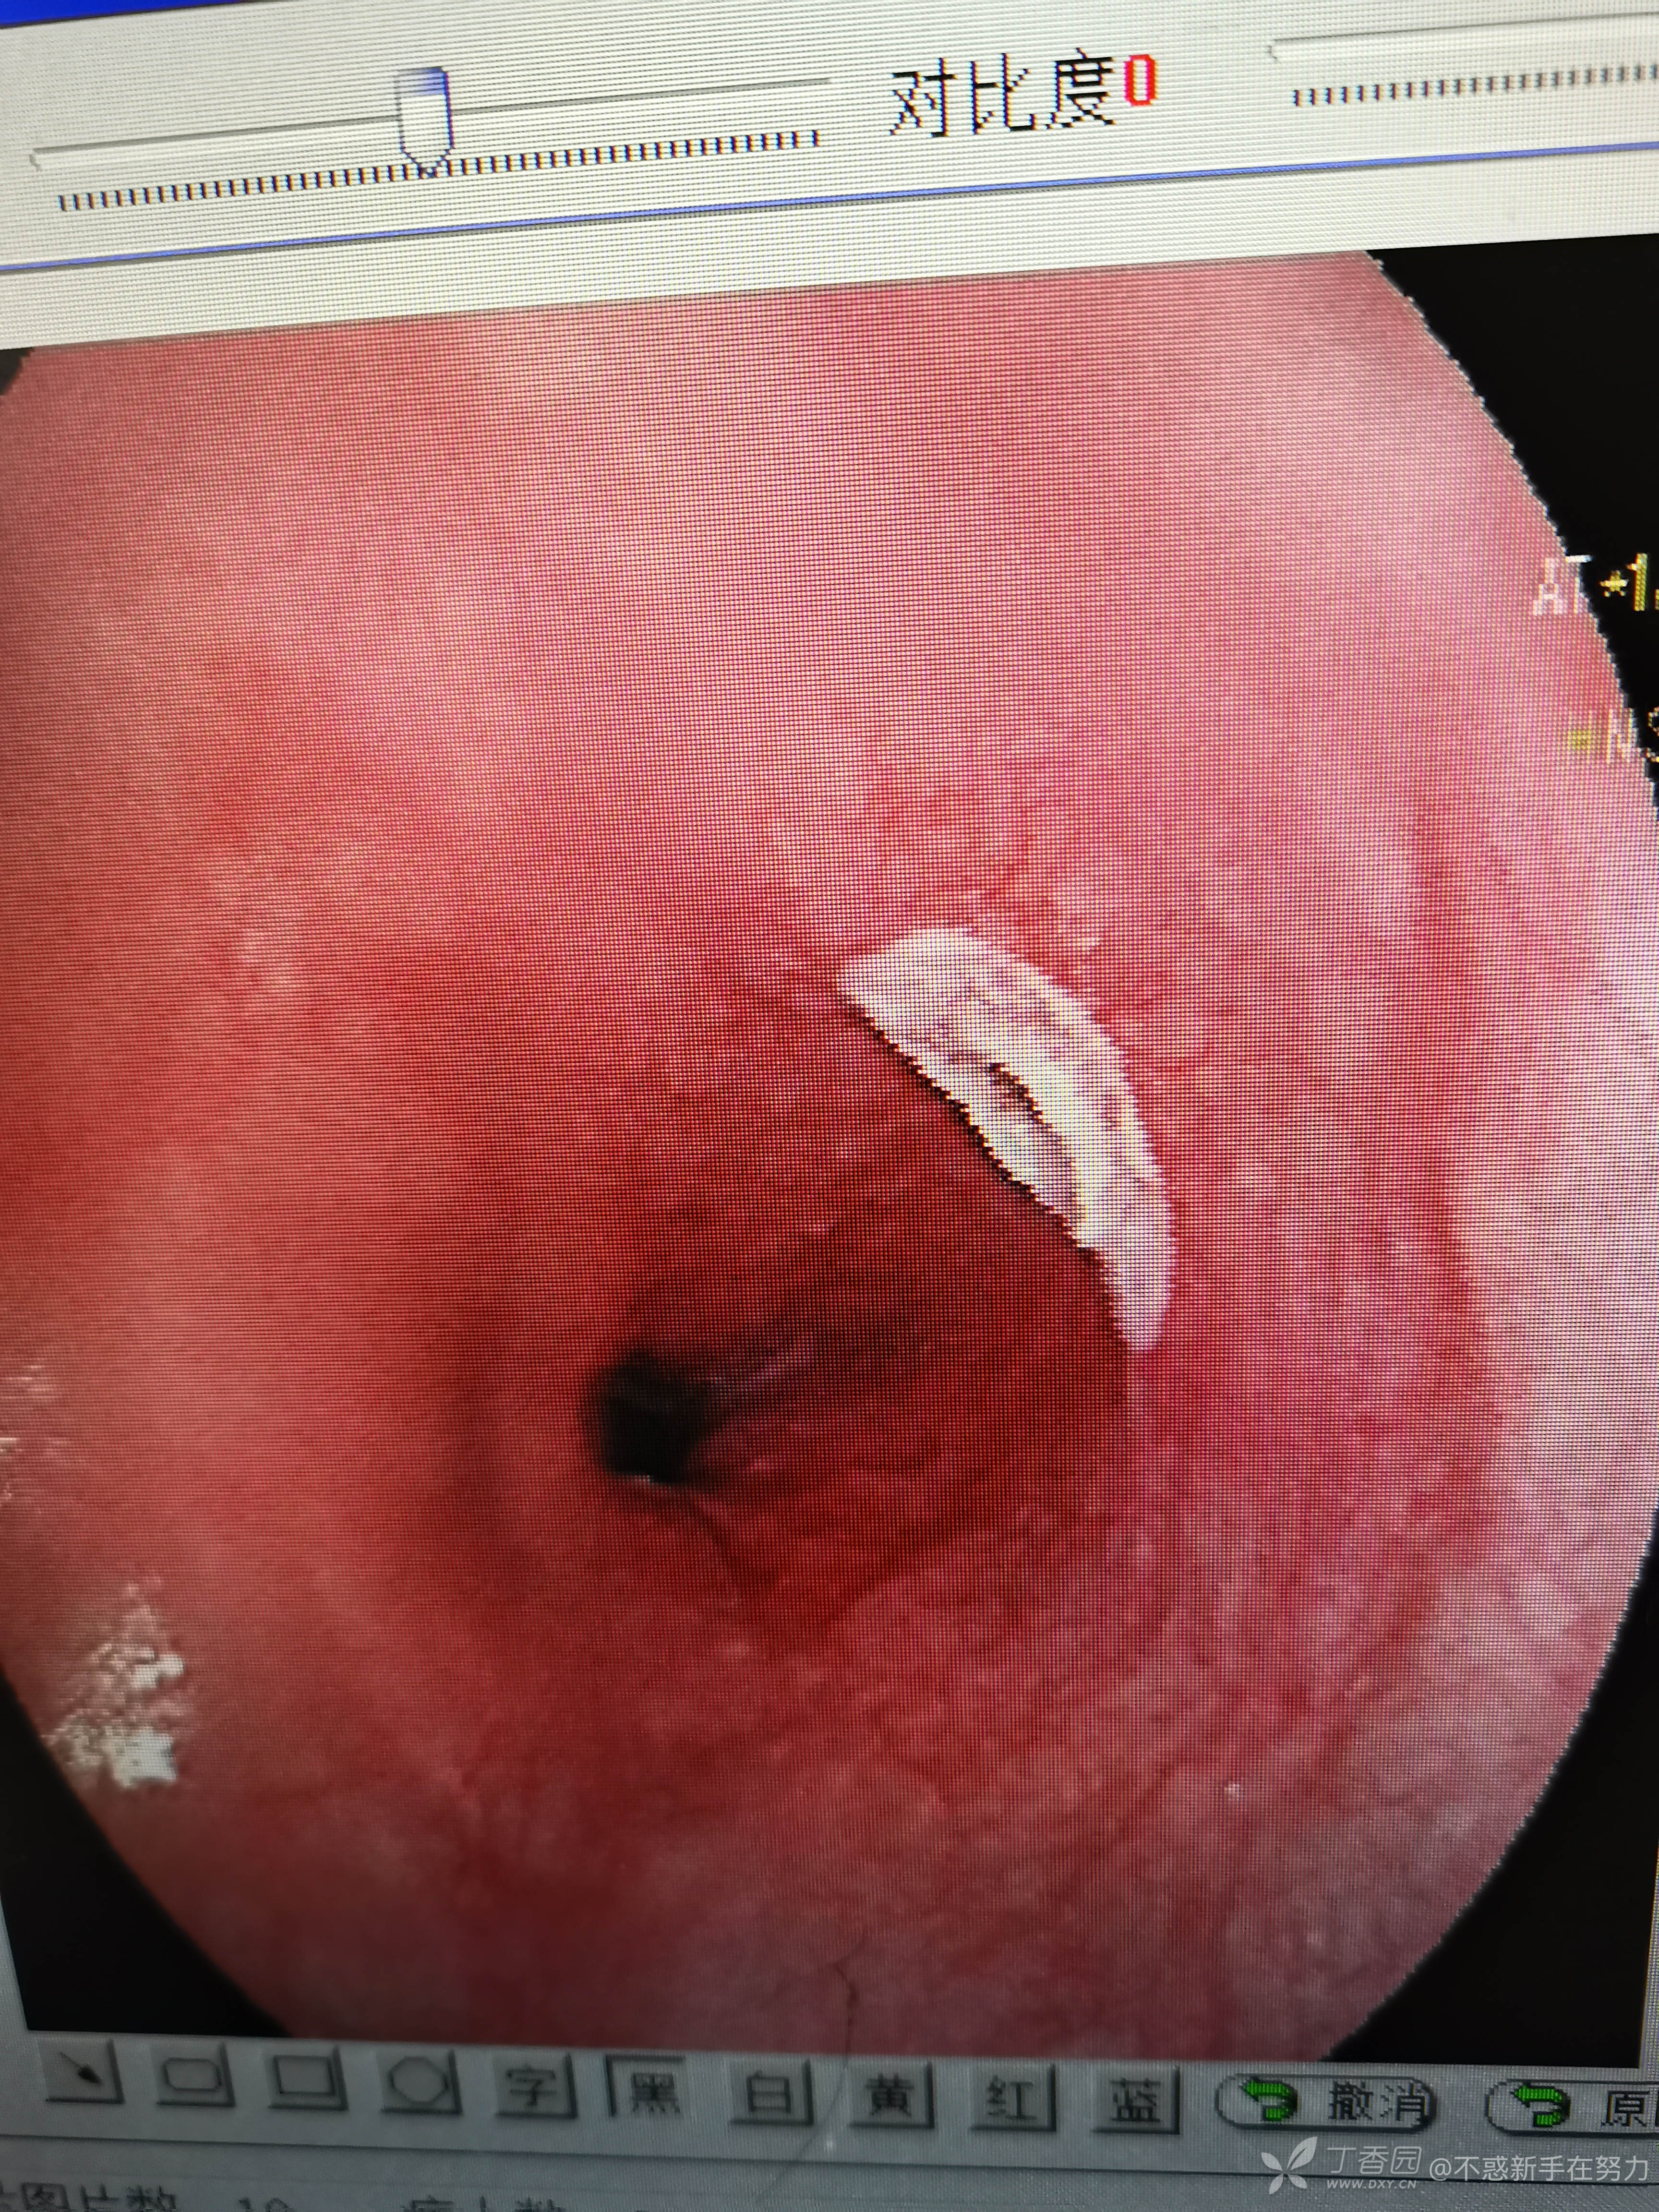

附带几张平常做的内镜下手术,都是简单的,见笑了!顺便来寻找一下自信心!毕竟这里这么多老师。